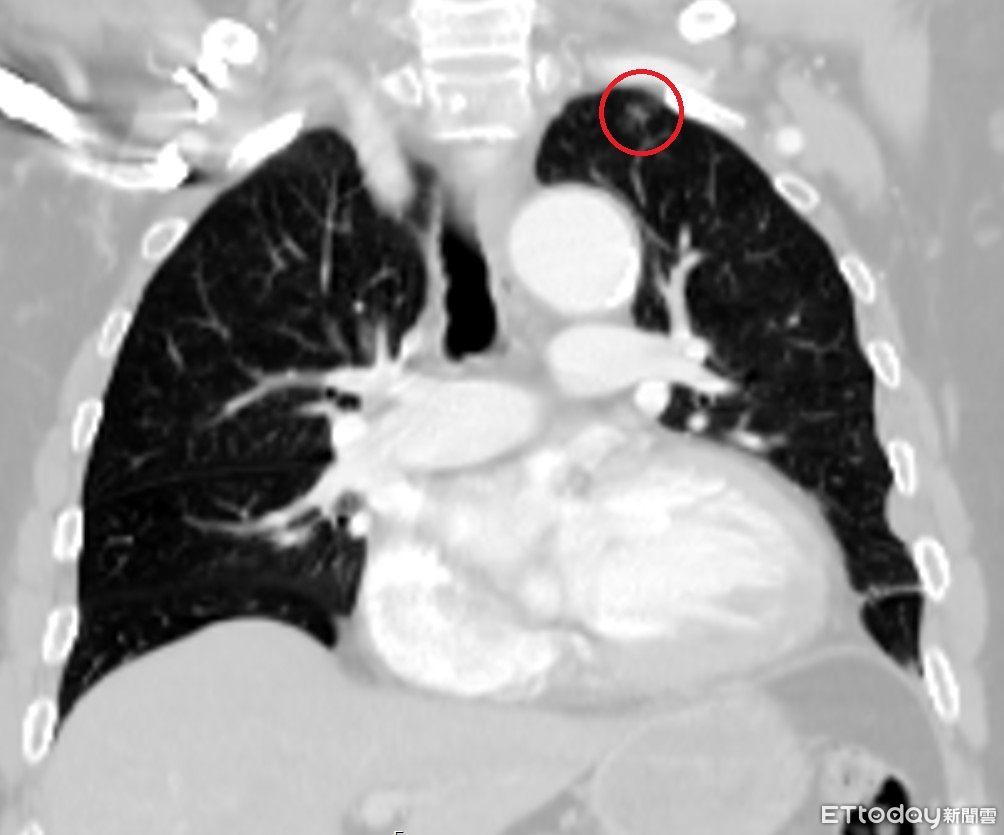

▲光田醫院搶救林男時,電腦斷層意外發現林男肺部邊緣出現一處僅0.9公分的肺結節陰影,事後證實是早期肺腺癌。(圖/光田醫院提供)

台中一名林姓男子因車禍造成肋骨多處骨折、胸腔積水,被送到醫院急救,結果就在醫師與影像醫學科團隊仔細檢視電腦斷層時,意外發現林男肺部有一個小於1公分的腫瘤,醫師進行手術搶命同時也切除腫瘤,最後病理報告也證實為肺腺癌,讓這個原本可能潛伏多年、毫無症狀的病灶,因車禍而被提早發現,讓男子免於癌王威脅。

林男的狀況屬於肺癌最早期的第一期,是所有肺癌分期中最輕微、預後最好的階段,不僅幾乎無症狀,治癒率極高。也正因為發現得早,處理及時,術後無需接受化療或放療,目前恢復良好,僅需定期追蹤觀察。